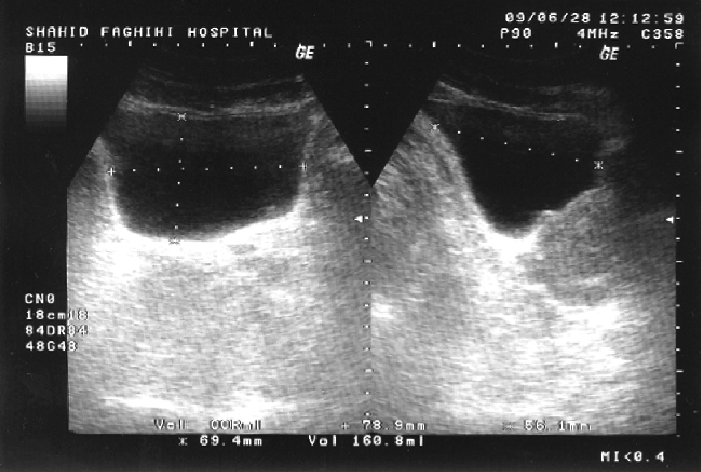

Comment mesurer le volume vésical

Mesurer la largeur (l) et la hauteur (h) en coupe transversale

Mesurer la longueur (L) en coupe longitudinale

Calculer le volume :

Volume (mL) = L × l × h × 0,52 (l'appareil fait le calcul automatique si le mode "Volume" est selectionné dans le menu)

📏 Repères pratiques :

-

> 300 mL : rétention significative

> 500–600 mL : globe vésical franc ➡️ impact immédiat : sondage urinaire (sauf contre-indication).

![]()

Mesure du volume vésical – Gauche: vue transversale avec mesure de la largeur et la hauteur. Droite: vue longitudinale avec mesure de la longueur. Baradaran-Ghahfarokhi M et al. Figure 1. Comparison of prostate and bladder volume measurements.